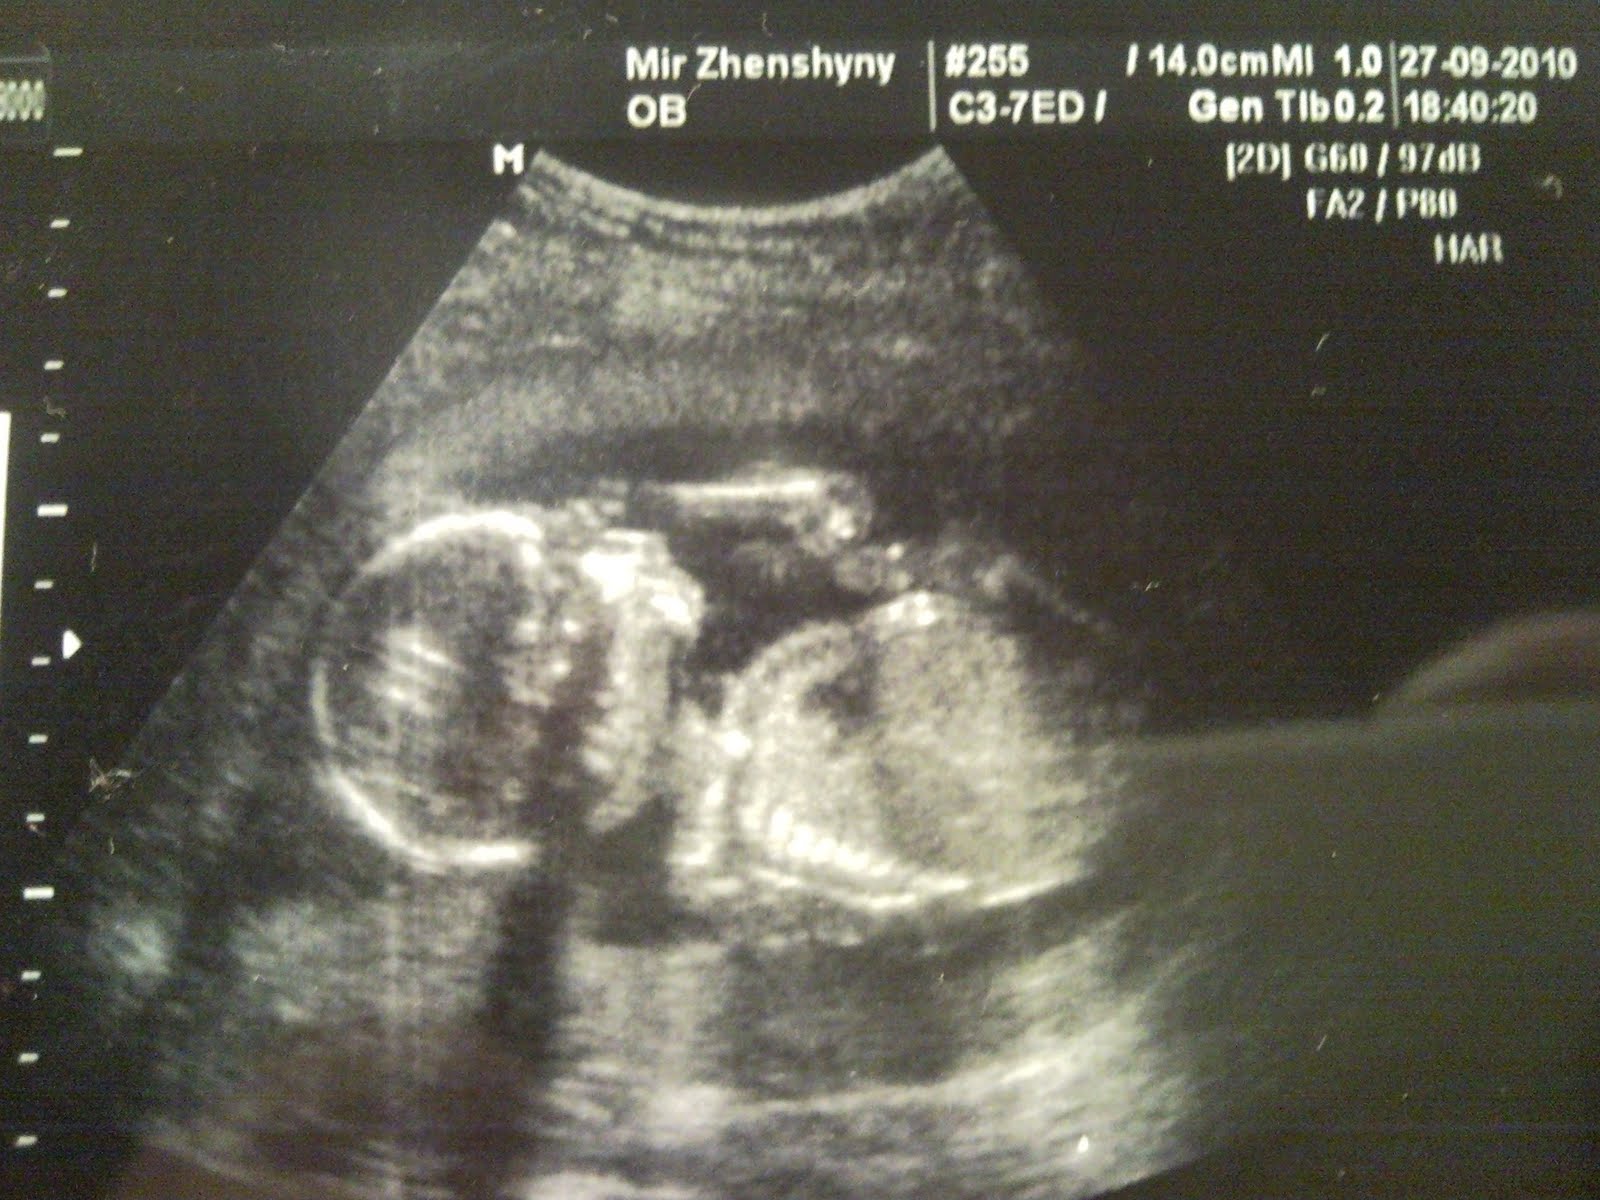

18 недель. УЗИ.